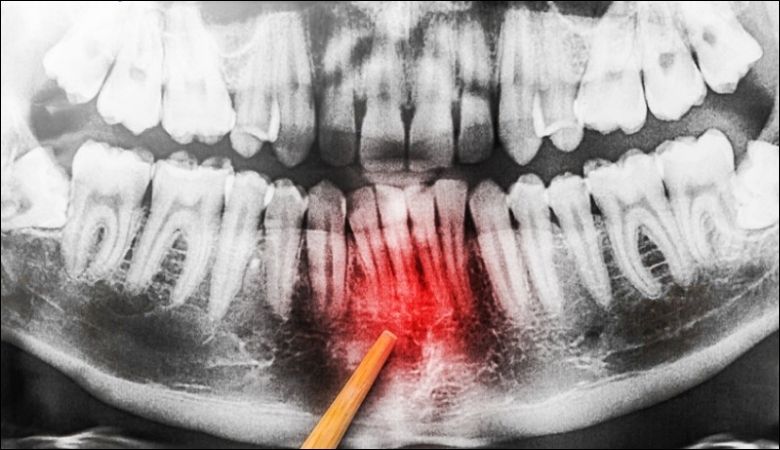

Nếu không điều trị, bệnh có thể gây tiêu xương ổ răng, dẫn đến mất răng vĩnh viễn.

Viêm nha chu có nguy hiểm không phụ thuộc vào mức độ bệnh và thời điểm can thiệp. Nếu không điều trị, bệnh có thể gây tiêu xương ổ răng, dẫn đến mất răng vĩnh viễn.

Ngoài ra, vi khuẩn từ viêm nha chu có thể xâm nhập vào máu, làm tăng nguy cơ bệnh tim mạch và tiểu đường, theo WebMD. Điều trị viêm nha chu sớm giúp giảm thiểu các biến chứng nguy hiểm này.